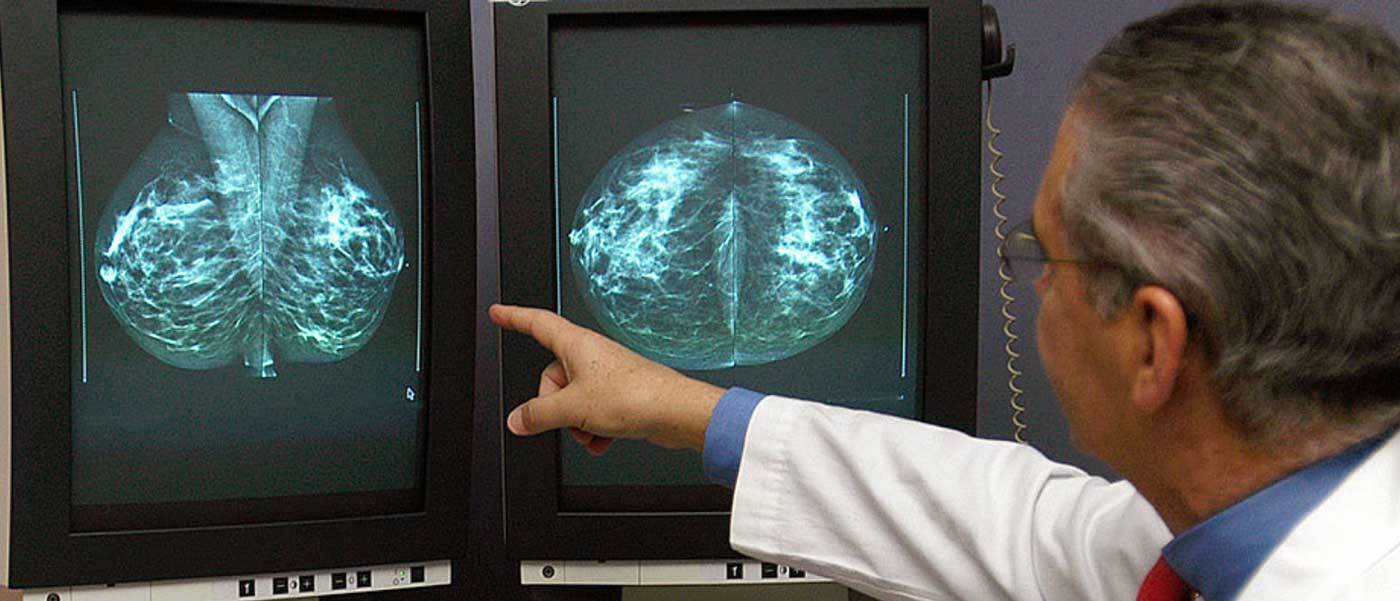

سلول های سرطانی پستان معمولاً توموری را تشکیل می دهند که به واسطه تصویربرداری دیده شده یا به شکل توده احساس می شود.

وی افزود: بیشترین ابتلا به این بیماری در بانوان در رده سنی 45 تا 55 سال است. در غربالگری سرطان سینه، زنان 30 سال تا 70 سال معاینه می شوند و در زنان بالای 40 سال توصیه می شود هر دو سال ماموگرافی انجام دهند.

این کارشناس افزود: تمامی زنان ۴۰ سال و بالاتر لازم است هر ۲ سال یکبار ماموگرافی انجام دهند، اما در افرادی که سابقه سرطان تخمدان و یا سرطان پستان در یک پستان را دارند و یا سابقه خانوادگی سرطان پستان، تخمدان، پروستات و لوزالمعده دارند، حتما باید غربالگری زودتر انجام شود.